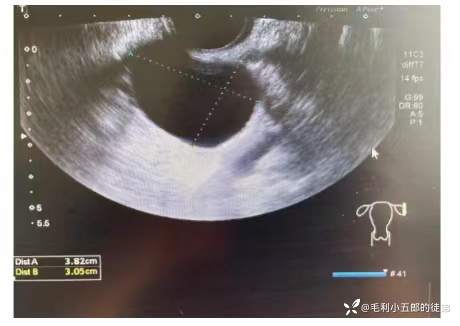

1.妇科超声(2023-5-30我院): 阴腹联合扫查:子宫后位,大小形态如常,内膜厚约: 0.7cm.肌层回声均质。左侧卵巢大小: 4.4x2.7cm。左侧附件区探及一无回声,大小约3.9x3.1cm,壁薄透声佳,其内未探及明显血流信号。盆腔探及一无回声,大小约29.8x23.1x19.8cm,透声佳,未见明显血流信号。左侧附件区囊肿,盆腔无回声,源于卵巢?

2.盆腔核磁(2023-5-30 我院):膀胱充盈良好壁不厚,腔内未见异常信号影。子宫呈前屈前倾位,子宫大小、形态正常,子宫内膜未见明确增厚,信号未见异常,结合带显示清晰,子宫未见异常信号影。扫描范围内腹盆腔内巨大囊性灶,边界清晰,DWI上可见囊壁呈环形高信号,与右侧卵巢分界不清,腹、盆腔脏器受压移位。左侧附件区类圆形异常信号影,T1WI呈等信号,T2WI呈高信号,大小约3.8x3.1cm,边界清晰。盆腔未见积液、未见肿大淋巴结。下腹腹盆腔内巨大肿块,考虑右侧附件来源,囊腺瘤可能,请结合临床。左侧附件囊性灶,考虑卵巢囊肿。